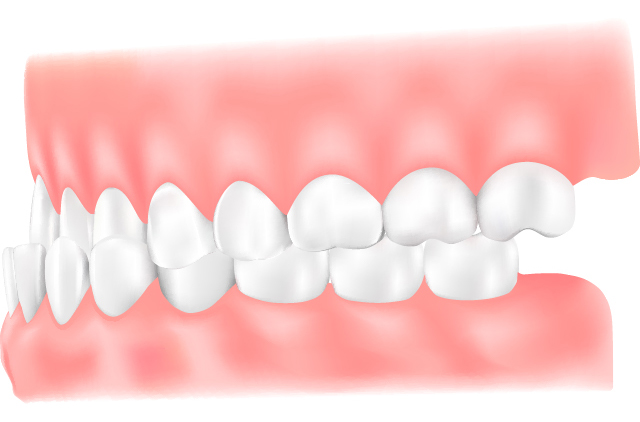

下顎前突(受け口)

上の歯より下の歯が前方に出ている状態で、上顎が小さい、または下顎が大きいことで起こります。噛みにくさや滑舌の悪さにつながることがあります。